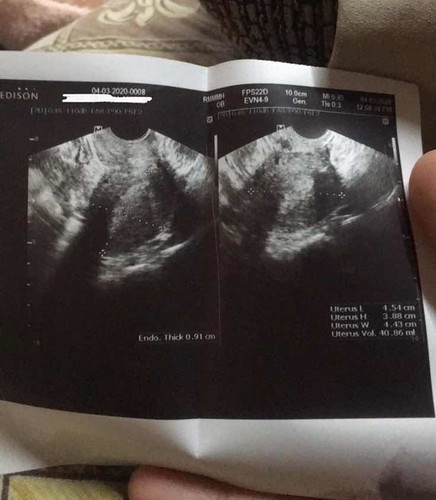

Tvs

Ako ung ngpost nito nung nakaraan, dami ngsabi na wala at dami nangbash kahit 1st time ko lng ngpost pero alam nyo ba na buntis ako at di nakita kahit 2 months na? Hindi naisama ung isang pic dahil sobrang bagal ng net ko at ngaun lng nakaopen ulit kaya salamat dun sa mga ngsalita ng di maganda dito at pasensya na kung ngaun ko lng kau nareplyan..